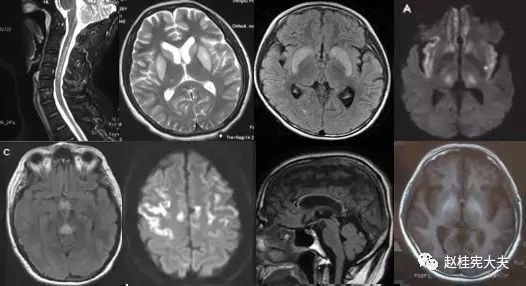

重要申明:以下每个部分会配磁共振图片,因疾病和影像之间存在同病异象、同像异病,为避免误导,图片不标注疾病,请各自鉴赏,另其中有部分图片来源于网络,有疑问可与本人联系。

一、M—metabolism 代谢性

代谢性脑病的原因很多,包括氨基酸、有机酸、脂肪酸、糖等代谢异常,以及线粒体功能障碍等,导致高氨血症、低血糖、酸中毒和能量缺乏,引起脑功能障碍。我们在临床上看到的有缺血缺氧性脑病、低血糖致白质脑病、肝性脑病、肾性脑病、Wernicke脑病、线粒体脑病等。中枢神经系统受累的病灶在磁共振上可出现各种表现。